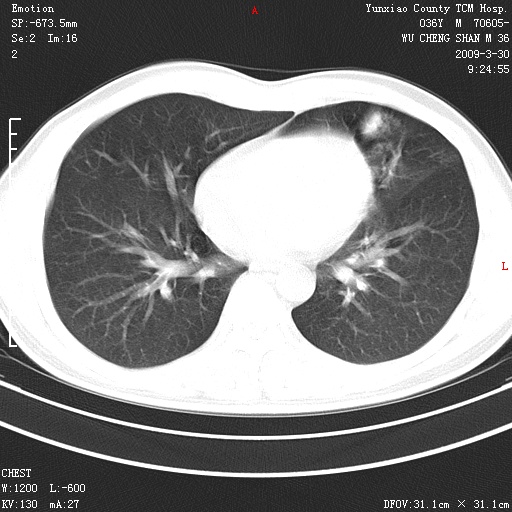

本院家属,胸痛,无咳嗽咳痰发烧病史,治疗一个月后病灶无明显改变,支气管镜示左肺慢性炎症,未见癌细胞,

胸痛,无咳嗽咳痰发烧病史,治疗一个月后病灶无明显改变,支气管镜示左肺慢性炎症,未见癌细胞,左肺下叶前段片状影,边缘不清,内见空支气管征,纵隔未见淋巴结肿大,周围无卫星灶,应考虑为炎性病变。

胸痛,无咳嗽咳痰发烧病史,治疗一个月后病灶无明显改变,支气管镜示左肺慢性炎症,未见癌细胞,左肺舌叶片状影,边缘不清,内见空支气管征,周围无卫星灶,应考虑为炎性病变。

考虑左肺上叶舌段及前段感染性病变;建议正规抗炎治疗后复查。

左肺舌叶片状影,边缘不清,内见空支气管征,炎性病变